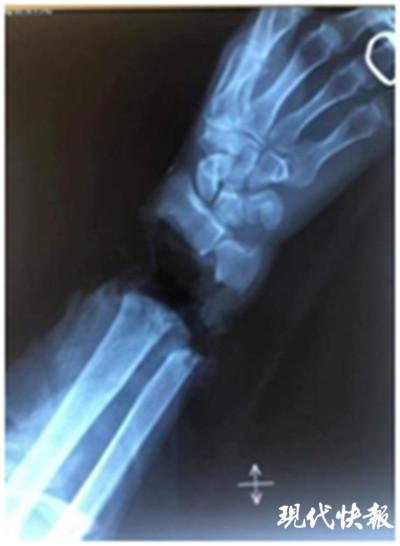

△蒋先生手腕被完全切断 常州一院供图

现代快报讯(通讯员 冯凯 记者 陆文杰)55 岁的蒋先生是个木工,在用电锯切割木块时,由于衣服不慎被卷入,导致左手从手腕处被电锯完全切断。常州一院创伤骨科主任何双华经过仔细检查,决定立即开展左腕离断伤断腕再植手术。手术团队经过 6 小时努力,成功进行了断腕再植手术,蒋先生的手保住了。

清创、修整、用钢板对断腕进行固定 …… 肢体离断后最佳抢救时间是 6~8 小时内,越早救治成功率越高,创伤骨科团队在与时间赛跑。"人体腕部共有 25 根肌腱,主要神经血管束 4 束,手术需先固定骨头断端,随后将每根肌腱、神经、血管进行吻合。整个手术需在显微镜下放大十几倍进行,所用的缝合线针粗 0.07mm,比头发丝还细很多。"何双华主任表示,"手术对医生的能力是个考验,要求术者必须精神高度集中,动作精细、准确、娴熟。"